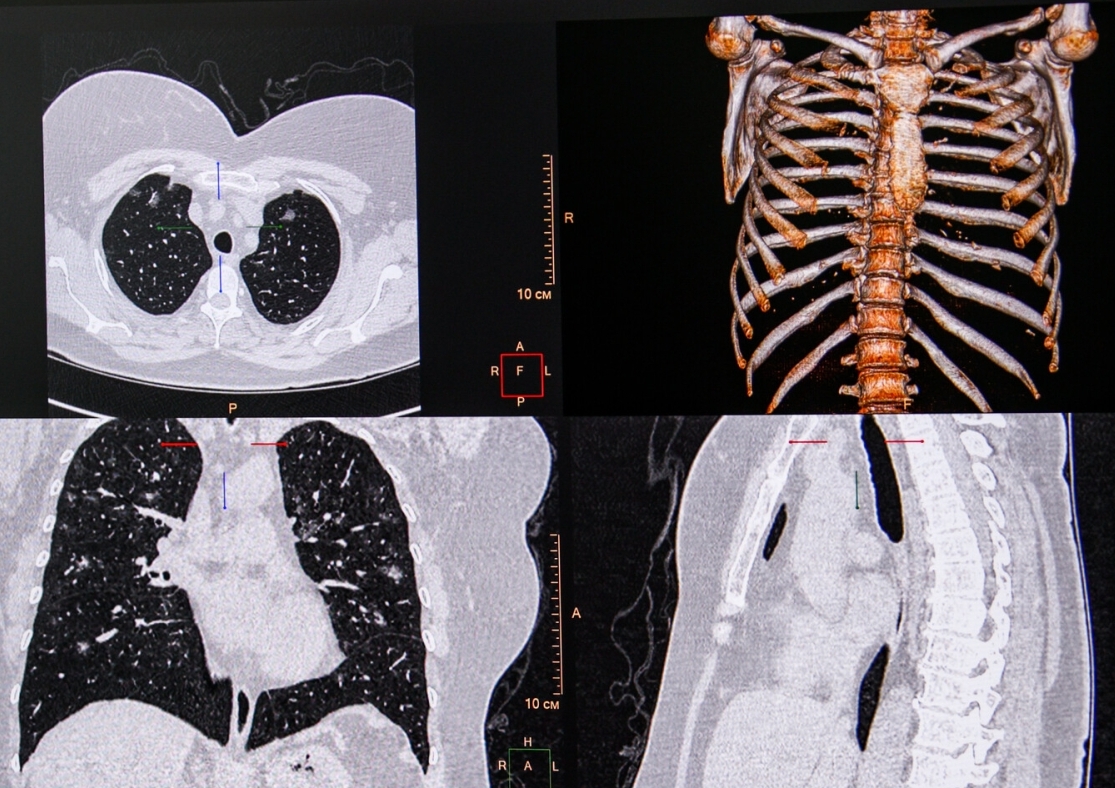

Затяжной коронавирус может вызывать долгосрочные повреждения легких, мозга и почек, говорится в новом британском исследовании, опубликованном в журнале Lancet. Тяжесть последствий инфекции напрямую зависит от сложности течения болезни, а также от возраста пациента и других проблем со здоровьем.

Спустя полгода после выписки патологические изменения на снимках МРТ были обнаружены у 61% пациентов, переболевших COVID-19. У тех, кто не переболел коронавирусом, только у 27% пациентов.

В частности, у выздоровевших после затяжного COVID-19 повреждения легких встречались почти в 14 раз чаще, повреждения мозга — в три раза чаще, а почек — в два раза чаще, чем у пациентов из контрольной группы.